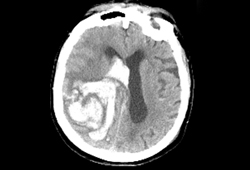

- noncontrast head CT